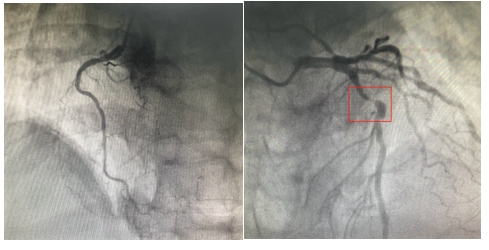

血管开通前

23:32分

血管造影显示:患者“三支血管病变”,前降支近段几乎闭塞,回旋支近段可见80%狭窄病变,右冠状动脉中段慢性闭塞。

23:38分

导丝通过病变血管,打通血管。从患者到达导管室门口至导丝通过(简称D2W),门丝时间仅用时13分钟!

血管开通后